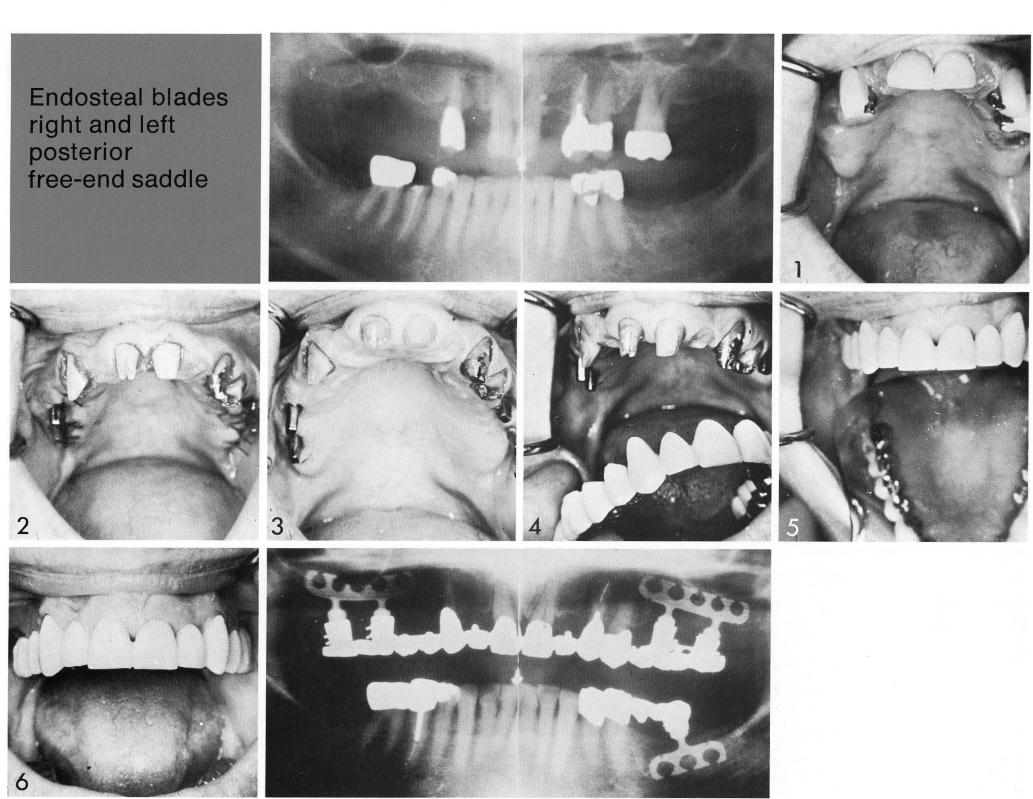

Endosteal blades.,

right and left posterior

free-end saddle

Originally it was hoped that a special shallow bladevent design could be used successfully in many cases with a low-flaring sinus. However, the shallow design has proven one of the least successful, principally because the loss of bone mass that precedes volume loss leaves very few, very fragile trabeculae under the sinus for blade-vent contact. Therefore a pterygoid extension type implant is preferred if a deep-bodied bladevent design can-not be used. Despite the drawbacks, a few shallow bladevent cases have succeeded, most noteworthy those with strong abutments in other sites. Here the natural teeth (1) and bladevents (2,3) are used. The right bladevent has been "customized" by cutting down its central legs to accommodate a particularly low drop in the sinus. Notice the change in the gingivae after the case was completed, compared to the poor periodontal and gingival condition of the patient while wearing a partial denture.

1 Maxillary bladevent implant customized to accommodate low drop in sinus